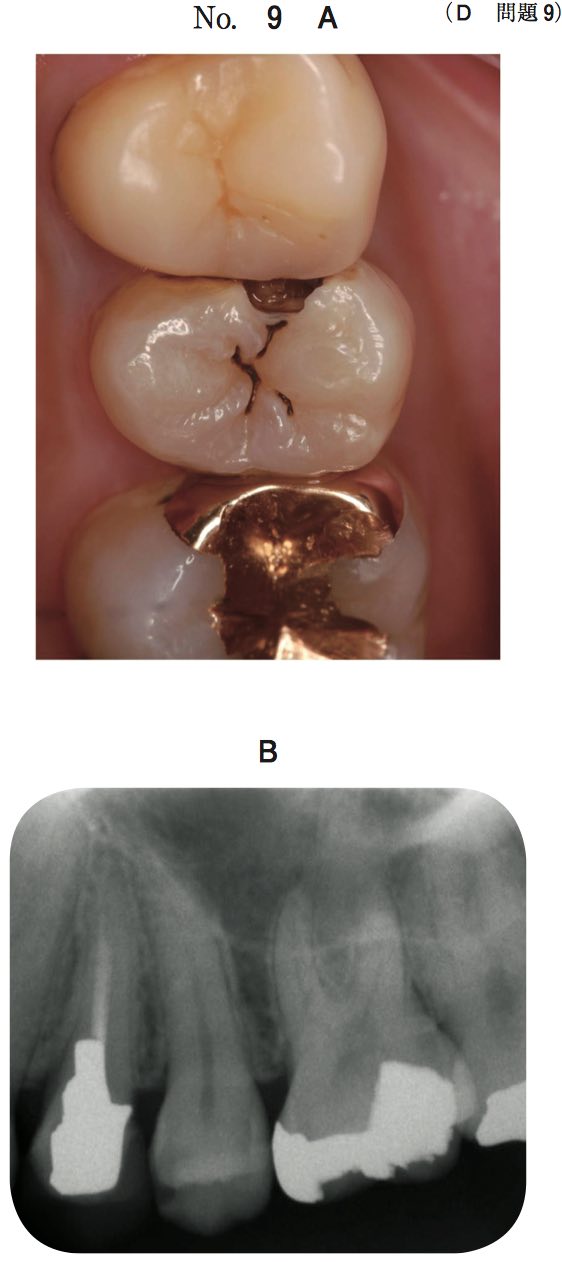

28歳の男性。下顎右側第一大臼歯の疼痛を主訴として来院した。3年前に治療を受けたが,数日前から30分ほどの自発痛が間欠的に起こるという。電気診で閾値が低下している。初診時の口腔内写真とエックス線写真とを別に示す。

軟化象牙質除去後の処置で適切なのはどれか。1つ選べ。

スクリーンショット 2017 01 19 16 04 58スクリーンショット 2017 01 19 16 05 03

A グラスアイオノマーセメントで裏層し,コンポジットレジン修復

B 水酸化カルシウムで間接覆髄し,コンポジットレジン修復

C 酸化亜鉛ユージノールセメントで間接覆髄し,コンポジットレジン修復

D 水酸化カルシウムで直接覆髄し,コンポジットレジン修復

E 酸化亜鉛ユージノールセメントで仮封し,経過観察

正答 E

問題文に「間欠的な自発痛」とあるので、CR修復など最終修復に進んではいけません。もし「自発痛」が「冷水痛」であればそれが正答になりえますが、今回の場合は、歯髄の炎症が大きいので、「歯髄鎮静療法」を選ぶ必要があります。鎮静療法につかえるお薬は、ユージノールとフェノール系の2種でしたね。ユージノールは歯髄炎が広まりかけている組織を殴って!黙らせるようなお薬です(アグレッシブ!)。それで歯髄炎が収まれば、歯髄保存しCR充填できますし、自発痛が止まらなければ全部性の歯髄炎に移行したと判断され、抜髄となります。

今回はとりあえず、ユージノールということでCかEが残ろいますが、Cのユージノール+CRは「重合阻害」を起こすのでアウトです!よって、正答はEとなりなす。

104B-4

35歳の男性。下顎右側第一大臼歯の違和感を主訴として来院した。2週前にう蝕の治療を受け,その数日後から自覚しているという。右下6はレジン系仮封材で充填されており,間欠的な咬合痛と冷水痛とがある。歯髄電気診に反応する。仮封材除去前のエックス線写真と仮封材除去前後の口腔内写真とを別に示す。適切な処置はどれか。1つ選べ

スクリーンショット 2017 01 19 16 07 27

スクリーンショット 2017 01 19 16 07 34a IPC法

b 抜髄法

c 直接覆髄法

d メタルインレー修復

e 光硬化型グラスアイオノマーセメント修復

正答 d

こちらは、歯髄が正常と判断できます。「自発痛」ではなく「間欠的な冷水痛」で、歯髄電気診で反応しているからです。よって、最終的な修復=メタルインレー修復にうつることができます。もちろん、歯髄に近接していて刺激が伝わってしまいそうなときには、間接覆髄や裏層などお薬をつめることを途中ではさむかもしれませんが、大枠の治療方針としてはメタルインレー修復が妥当となります。問題文の冷水痛が、自発痛だったりすると、「歯髄鎮静療法」や「抜髄」を考えていかなければならなくなります。